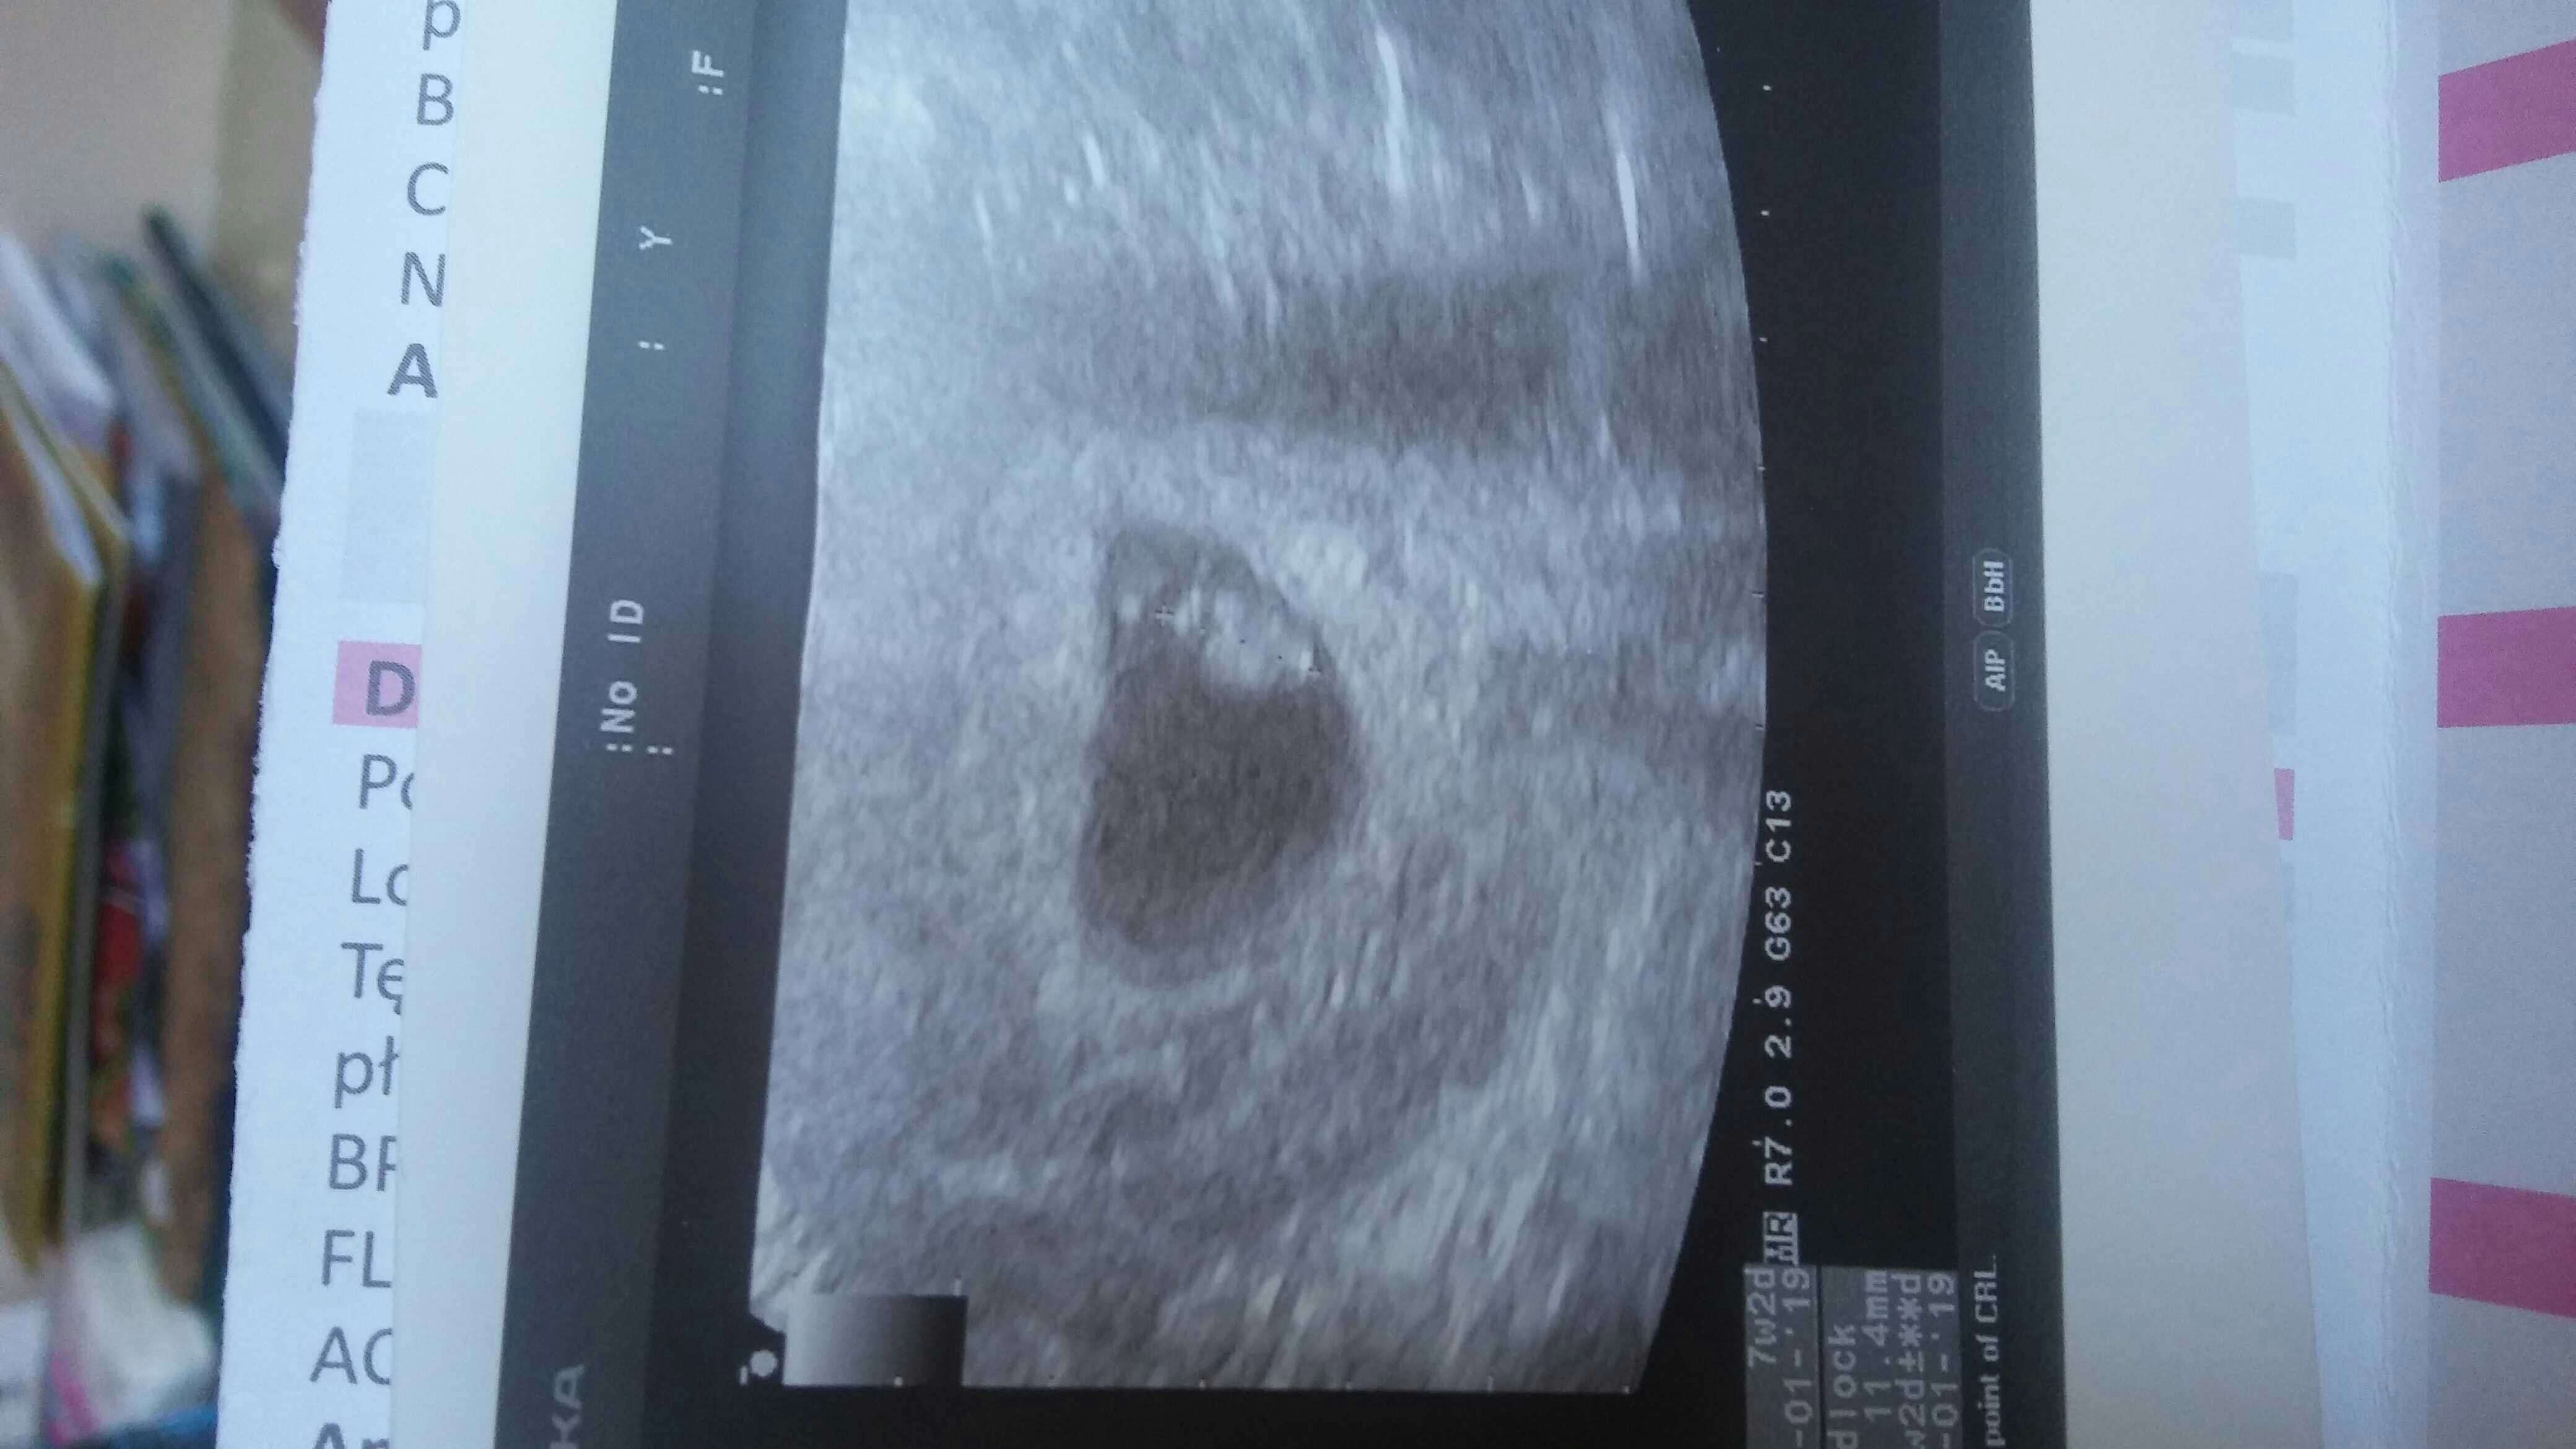

cieszę się że wszystko w porządku